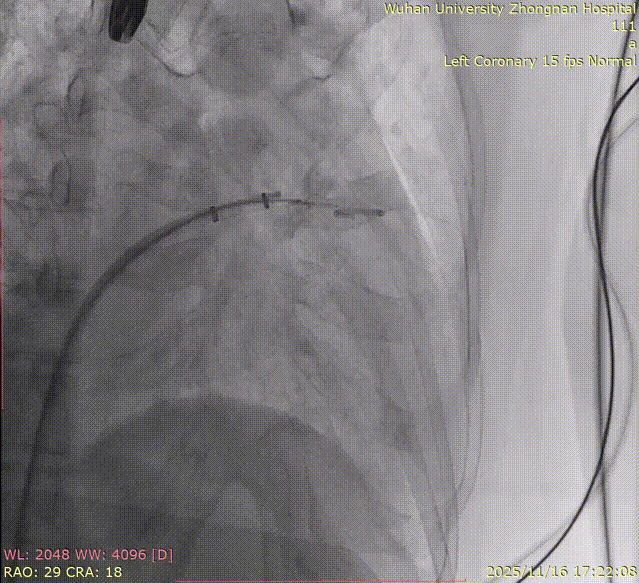

5.Right coronary angiography confirming no impact on the RCA after clipping.

8.Right coronary angiography confirming no impact on the RCA before releasing the second implant.